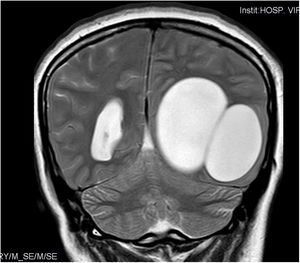

Caso clínicoMujer de 29 años procedente de Europa del Este (Rumanía), que acude al Servicio de Urgencias con un cuadro de cefalea intensa occipital izquierda, irradiada a la nuca, de varias semanas de evolución. Refiere una intensificación de la misma durante la última semana hasta hacerse invalidante, acompañada con vómitos. En la anamnesis dirigida describe pérdida de visión progresiva de 4meses de duración, detectándose en la exploración física una hemianopsia homónima derecha. Se le realizó un estudio de neuroimagen mediante tomografía computarizada (TC), observándose una gran estructura quística de localización temporo-occipital izquierda (fig. 1).

Durante su estancia en el hospital se completó el estudio de imagen con una resonancia magnética (RM), donde se observó una lesión quística polilobulada parietooccipital izquierda sin edema alrededor. Posteriormente, se objetiva otra masa a nivel del mediastino. Ante la sospecha diagnóstica de hidatidosis se le realizó una serología de anticuerpos frente a E. granulosus mediante hemaglutinación indirecta, cuyo resultado fue negativo. La paciente fue intervenida extirpándose 2quistes cerebrales. La técnica de exéresis se llevó a cabo mediante la realización de una cortectomía lineal craneal al límite superior de los quistes y, posterior resección de la banda de parénquima cerebral malácico que cubría el polo posterior de los mismos, consiguiendo de esta manera la exposición de ambos. El siguiente paso fue la disección de ambos quistes de las adherencias de su cara profunda al cerebro. Para ello se utilizó la «técnica de Dowling», consistente en la inserción de un catéter en el plano virtual entre el cerebro y el quiste, para una vez ubicado realizar la inyección progresiva de suero fisiológico por el catéter y así conseguir la separación paulatina del quiste (fig. 2). Mediante esta técnica se pudo resecar ambos quistes sin la rotura de ninguno. Uno de ellos se envió al laboratorio de Parasitología para un diagnóstico de certeza (fig. 2).

El estudio de imagen se compone de TC y RM, como las principales técnicas utilizadas en la afectación cerebral. También existe la posibilidad de realizar una radiografía convencional, aunque con esta técnica solo se podrá detectar la presencia de quistes calcificados, que aparecen aproximadamente en el 1% de los casos15. En el examen por TC y RM, los quistes presentan clásicamente una apariencia esférica, ocasionalmente ovoide, con una pared clara, blanda y elástica, y en su interior se aprecia un líquido cuya densidad se asemeja a la del líquido cefalorraquídeo. Se caracterizan, además, por no presentar realce tras la inyección de contraste ni asociarse con edema perifocal9,15. La Organización Mundial de la Salud establece una clasificación, donde ordena el estadio del quiste en función de su actividad y así ayudar a la elección de la estrategia terapéutica y seguimiento; esta clasificación se utiliza sobre todo en casos de hidatidosis hepática, donde el diagnóstico puede realizarse mediante ecografía abdominal2.